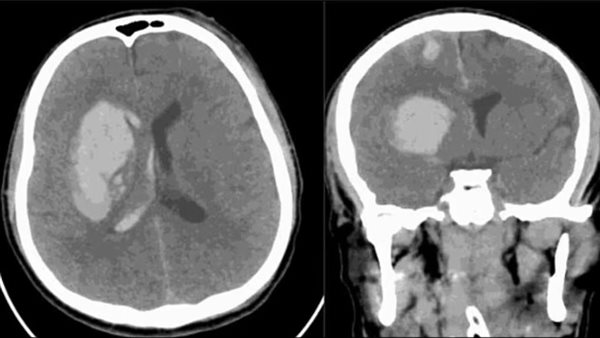

كما أن الحالة التي أبلغ عنها مستشفى صقر في رأس الخيمة تعود لرجل يبلغ من العمر 34 عامًا، أصيب بعدوى الفطر بعد نحو ثلاثة أشهر من تعرضه لإصابة دماغية في حادث سير، ونُقل المريض إلى العناية المركزة وهو يعاني من نزيف حاد في الدماغ وجروح عميقة في فروة الرأس، وخضع لجراحة عاجلة لتخفيف الضغط عن الدماغ.

بعد سلسلة من العمليات والعلاجات بالمضادات الحيوية، أظهرت الفحوص في اليوم الـ99 من دخوله المستشفى إصابته بـC. auris، ونجح الفريق الطبي في القضاء على العدوى باستخدام مزيج من العلاجات المضادة للفطريات على مدى عدة أسابيع، ليغادر المريض المستشفى بعد سبعة أشهر من العلاج.